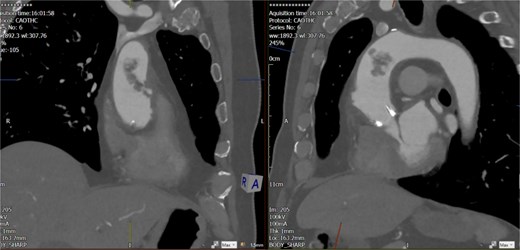

The echocardiogram showed no valve vegetation or mural thrombus. However, CT angiography of the thoracic aorta (Figs 3 and 4) revealed focal ulceration in the ascending aorta (1.3 cm) with an associated intraluminal filling defect (3.5 cm), appearing unstable. Additional small ulcerations and soft tissue were cuffing around the ascending aorta, with anterior mediastinal stranding suggestive of aortitis.

Unstable focal ulceration (1.3 cm) with a 3.5 cm intraluminal filling defect in the ascending aorta. Additional small ulcerations and periaortic soft tissue cuffing are present, along with anterior mediastinal stranding indicative of aortitis.